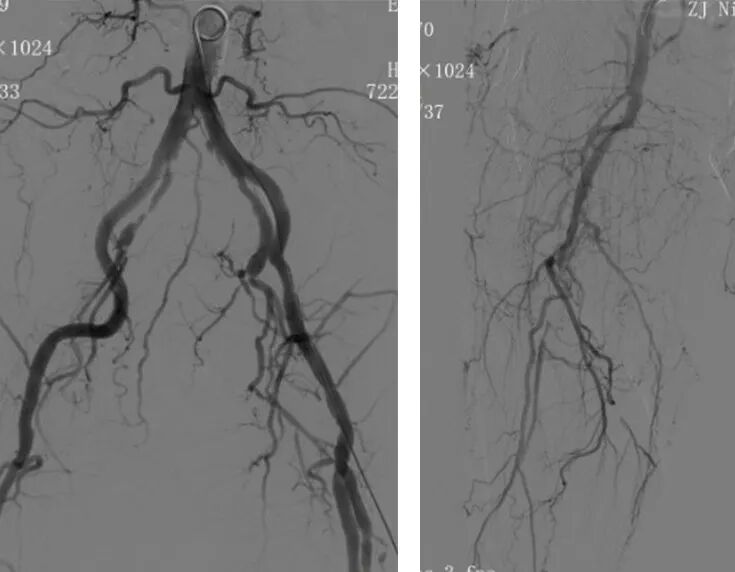

1、左股动穿刺置入猪尾导管造影双髂动脉及右下肢动脉,造影见右股浅动脉长段闭塞,腘动脉显影尚可,膝下胫前动脉显影,胫后及腓动脉未显影。

2、交换6F翻山鞘后,单弯导管配合导丝拟开通右股浅动脉病变,术中开通右股浅动脉近端时阻力较大,单弯导管配合泥鳅导丝下行距分叉5cm左右处下行困难,遂交换0.035系统支撑导管成袢下行通过。

3、0.018系统导丝建立工作路径后,予以3/4mm长球囊预扩张右股动脉病变,发现股浅近端造影剂滞留现象。

4.进一步造影见右股浅动脉近端瘤样扩张,伴局部造影剂滞留现象。